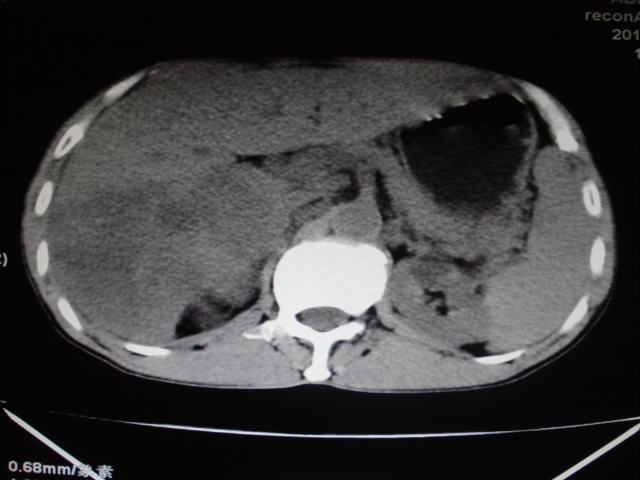

男性,62岁。肝右叶占位,平扫及增强如下,延迟期为15分钟扫描。